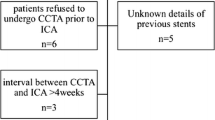

The study protocol was approved by our Institutional Review Board, and informed consent was obtained from all patients. In this prospective study, 57 consecutive patients that had previously undergone coronary stent implantation were evaluated for regular follow-up between June 2011 and September 2012. Patients were randomly divided by a computer-generated list into three groups by scanning protocol, that is, 100 kVp prospective CCTA (P-CCTA), 100 kVp retrospective CCTA (R-CCTA), or 120 kVp P-CCTA groups.

Patients with a history of previous allergic reactions to iodinated contrast media, impaired renal function (serum creatinine concentration > 1.5 mg/dL), hemodynamic instability, irregular heart rate (atrial fibrillation or frequent premature beats), or an inability to breath-hold were excluded. We also excluded a patient with a gold-coated stent (n = 1) because artifacts are most pronounced for tantalum, gold, or gold-coated stents [11], and patients with significant in-stent restenosis (n = 3).

Finally, a total of 101 stents in 53 patients were included in this analysis: 28 stents were scanned by 100 kVp P-CCTA, 39 stents were scanned by 100 kVp R-CCTA, and 34 stents were scanned by 120 kVp P-CCTA.